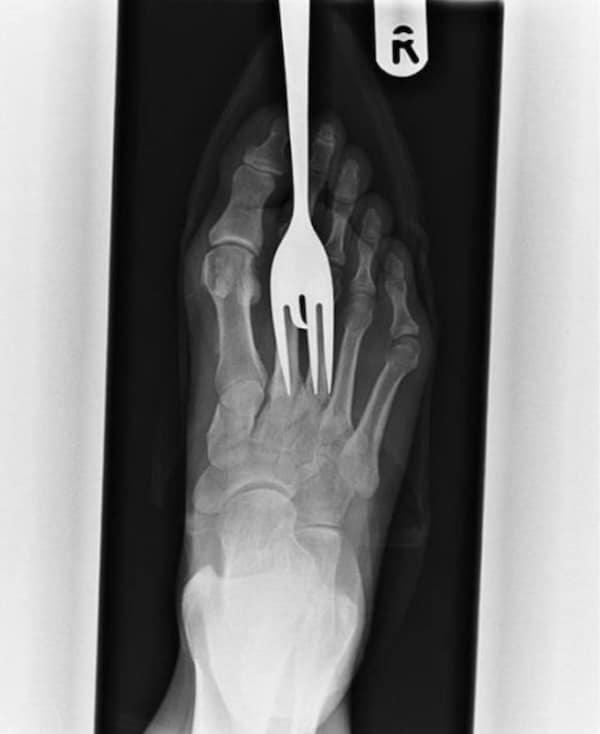

Weird xray photos

I used to think that nothing could surprise me anymore—until I stumbled upon some weird x-ray photos that made me reconsider my stance on human ingenuity (or lack thereof). Apparently, some people have a knack for getting objects lodged where they absolutely shouldn’t be. If you’ve ever wondered how not to use everyday items, these images might provide some unintended guidance.

This collection showcases 31 bizarre x-ray images that defy logic and anatomy textbooks alike. Each photo reveals unexpected objects making cameo appearances inside the human body, turning medical imaging into a gallery of the absurd. From common household items inexplicably found in unusual places to anomalies that would leave even seasoned doctors scratching their heads, these images offer a perplexing glimpse into the more “creative” side of medical emergencies. They highlight the intersection of curiosity, misadventure, and perhaps a dash of poor decision-making, all captured through the lens of radiology.